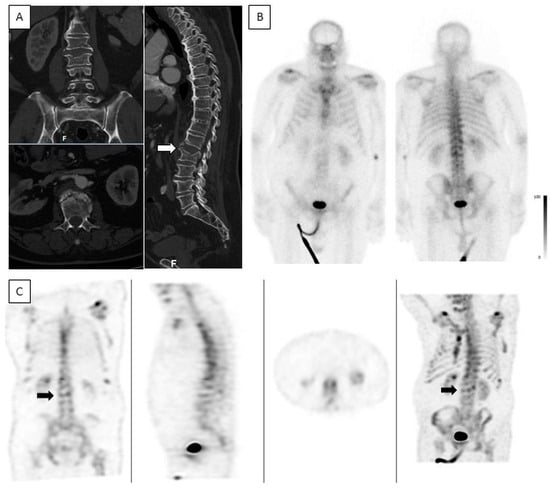

Figure 7. Low-intensity uptake in an acute ankylotic VCF. A 72-year-old male. CT was acquired on the day of injury and bone scintigraphy was performed 3 days after the injury. (A)—Coronal, axial, and sagittal spine CT show an acute ankylotic fracture in L2 and a fracture involving an osteophyte in L1 (white arrow). (B)—Planar anterior and posterior bone scintigraphy do not show any increased uptake in L2. (C)—Coronal, sagittal, axial, and MIP SPECT show only low-intensity uptake in L2 (black arrow).